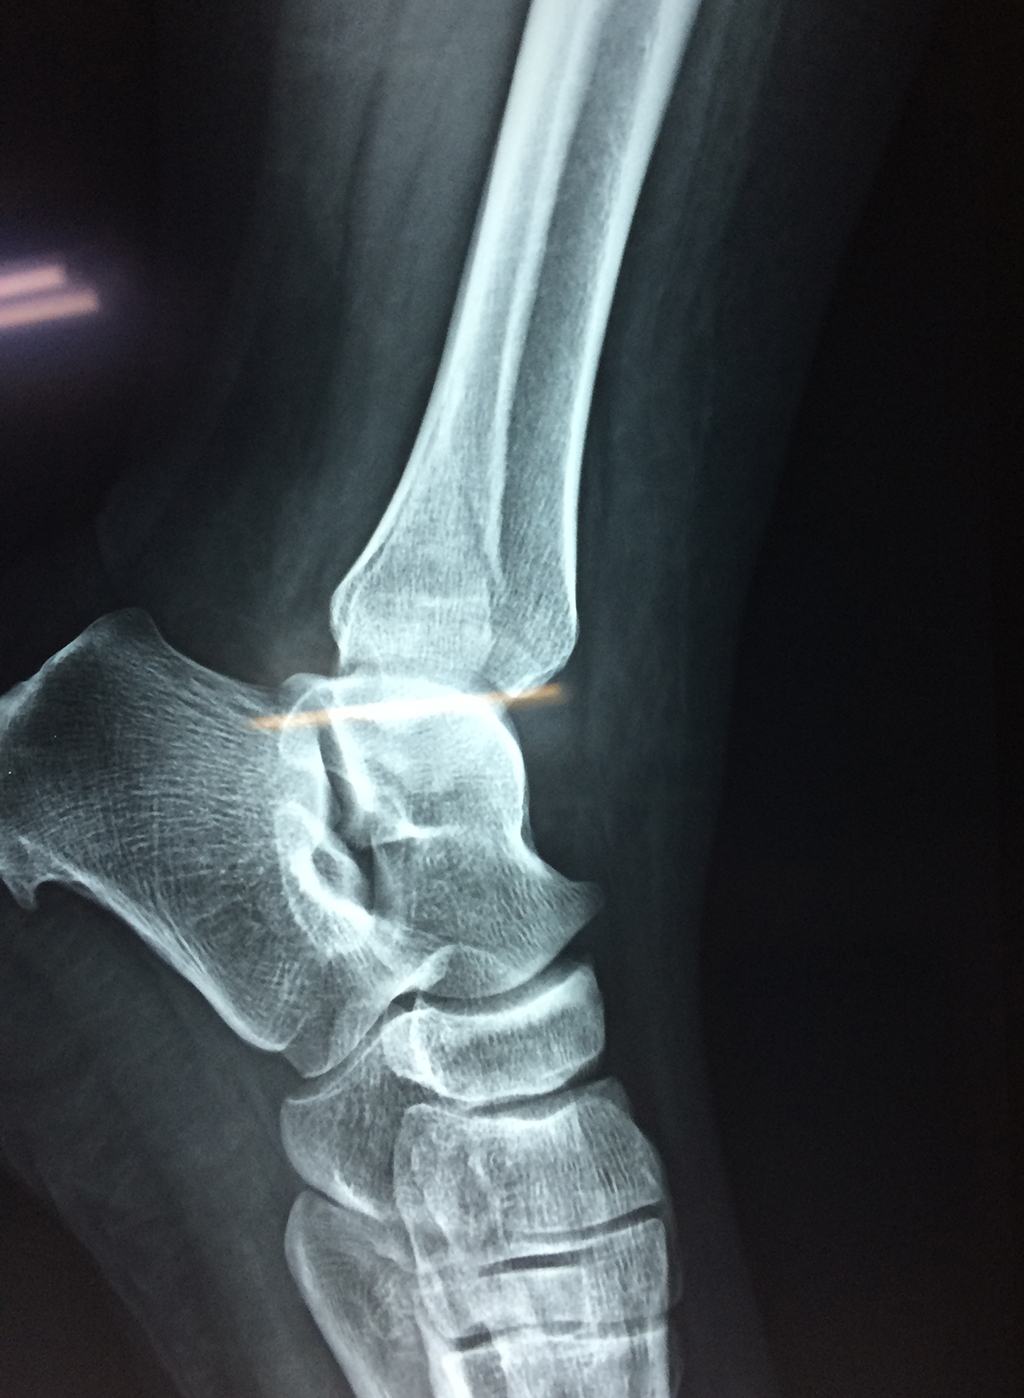

Una fractura de tobillo es la rotura de uno o más de los huesos del tobillo. Estas fracturas pueden ser:

Algunas fracturas de tobillo pueden requerir cirugía si:

- Los extremos de los huesos están desalineados entre sí (desplazados).

- La fractura se extiende hasta la articulación del tobillo (fractura intra-articular).

- Los tendones o ligamentos (tejidos que sujetan los músculos y los huesos entre sí) están rotos.